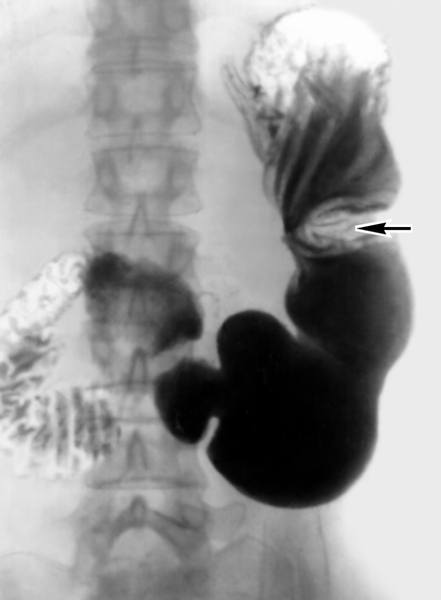

K25 Gastric ulcer, K25.

- Стандарт специализированной медицинской помощи при язвенной болезни желудка, двенадцатиперстной кишки

- Стандарт медицинской помощи больным с язвой желудка (при оказании специализированной помощи)

- Стандарт медицинской помощи больным язвой желудка и двенадцатиперстной кишки